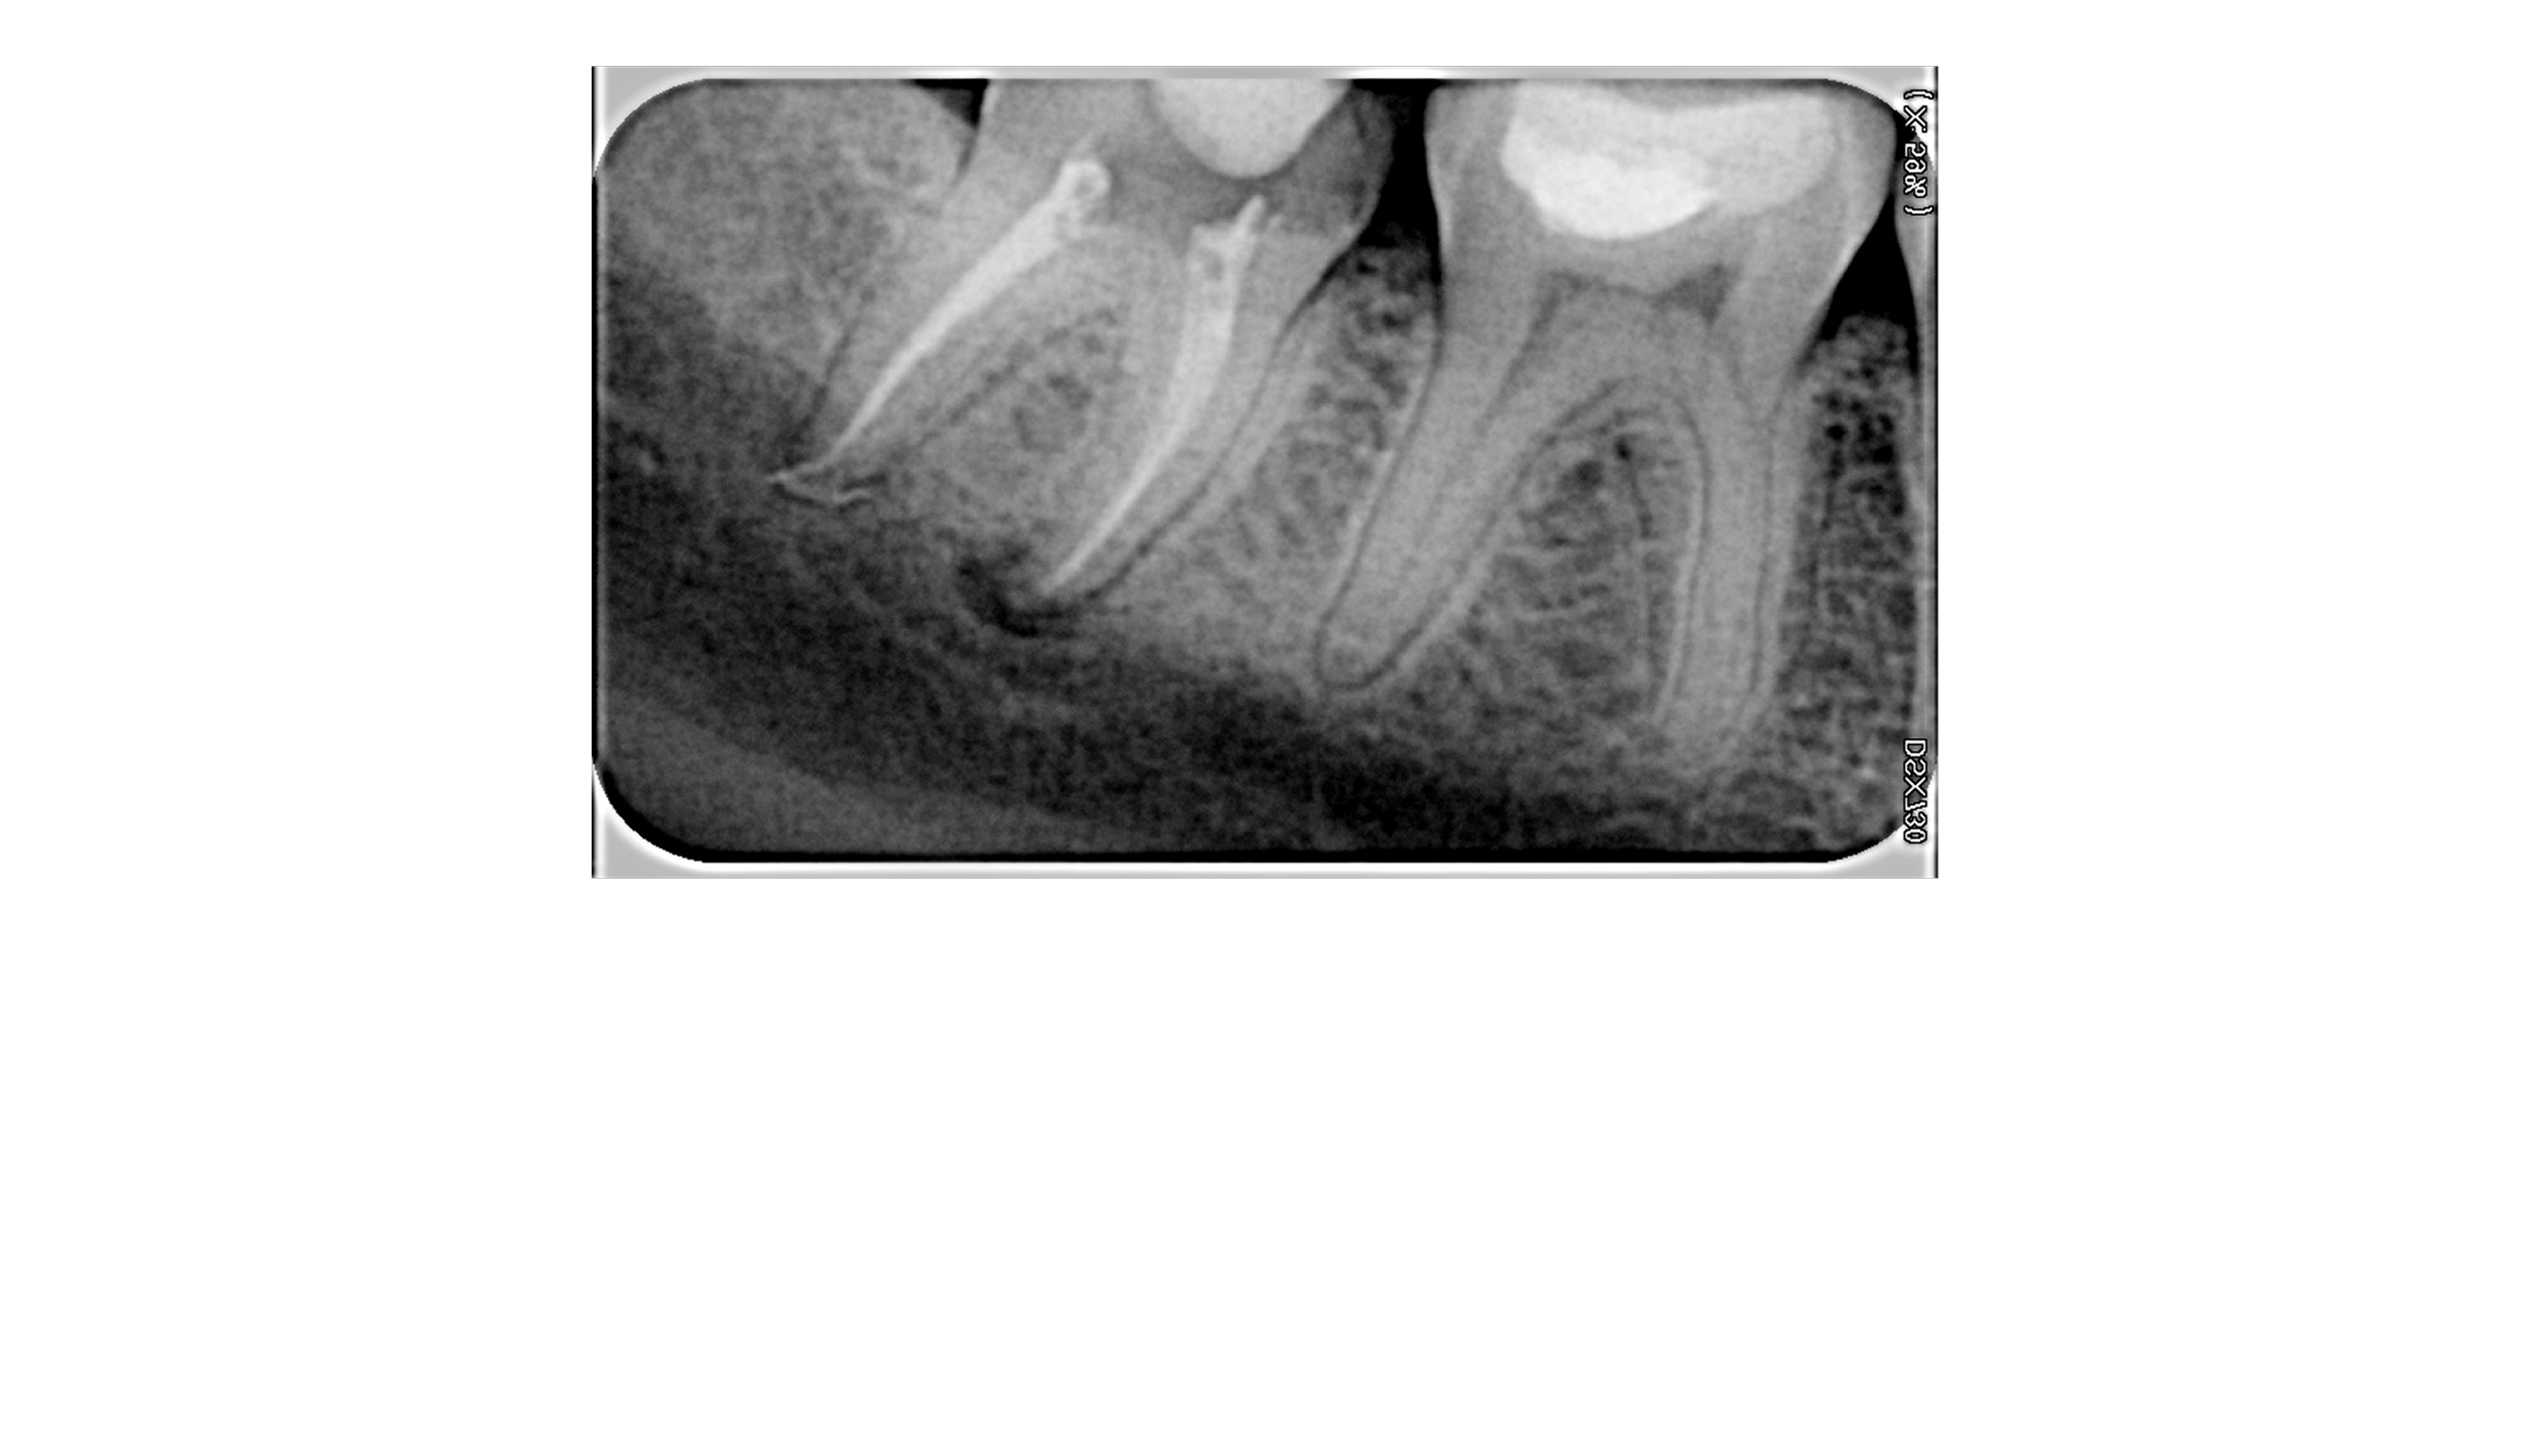

Прицельный снимок

Прицельный снимок иначе называют дентальной визиографией, так как он проводится с помощью радиовизиографа — рентгеновского аппарата, принимающего рентгеновские лучи на электронный сенсор (цифровая система SIDEXIS). Благодаря этому рентгеновский луч минимально рассеивается, а результат исследования мгновенно отображается на мониторе компьютера. Данная технология позволяет увеличивать снимок, обрабатывать и хранить неограниченное количество времени.

Прицельный снимок важен для постановки точного диагноза. Без предварительно сделанного рентген-снимка возможно проведение неверного лечения с соответствующими последствиями.

Прицельный снимок зуба — это быстрая и точная диагностическая процедура, позволяющая детально изучить состояние 1-2 зубов. Исследование занимает всего 2-3 минуты и абсолютно безболезненно для пациента.